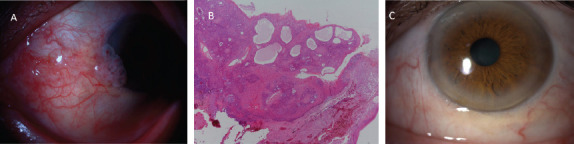

随着时间的推移,移植手术在世界范围内越来越普遍;器官移植增加了罹患恶性肿瘤的风险。这一现象主要是由于免疫抑制治疗所致,而免疫抑制治疗是预防移植排斥反应的主要方法之一。本研究旨在描述肾移植患者经组织学证实的眼表面鳞状细胞瘤(OSSN)的临床症状和体征。本文介绍了三位曾接受肾移植手术并被确诊为眼表鳞状上皮瘤的患者。所有病例的组织病理学检查结果均确诊为鳞状细胞瘤。经过手术切除、冷冻治疗和羊膜重建后,所有患者均未复发。实体器官移植患者需要接受严格的免疫抑制治疗,以防止移植排斥反应。免疫抑制治疗会增加罹患继发性恶性肿瘤(包括 OSSN)的风险。让所有移植患者了解这些风险非常重要。尽管众所周知 OSSN 是一种相对良性的作用肿瘤,很少转移到远处器官,但如果在免疫力低下的患者身上发生,临床病程可能会发生变化。因此,应监测这些患者眼表是否有肿块形成。完全切除的手术治疗可使肿瘤完全消退。

Transplantation surgery becomes more widespread with time worldwide; organ transplantation increases the risk of developing malignancies. This phenomenon is primarily due to immunosuppressive treatment which is one of the mainstay approaches to prevent transplant rejection. It is aimed to describe clinical signs and symptoms of histologically proven ocular surface squamous neoplasia (OSSN) in renal transplant patients. Three patients, who previously underwent renal transplant surgery, diagnosed with OSSN are presented. The histopathological examination results were conclusive for squamous cell neoplasia in all cases. No recurrence in any patients was observed after total surgical excision, cryotherapy, and reconstruction with amniotic membrane. Solid organ transplant patients undergo intense immunosuppressive treatment to prevent transplant rejection. That immunosuppressive treatment increases the risk of developing secondary malignancies including OSSN. It is important to inform all transplant patients about these risks. Even though OSSN is known to be a relatively benign acting tumor that rarely metastasizes to distant organs, the clinical course might change if it develops in an immunocompromised patient. For this reason, these patients should be monitored for any formation of a mass on the ocular surface. Surgical management through complete excision can result in the complete resolution of a tumor.